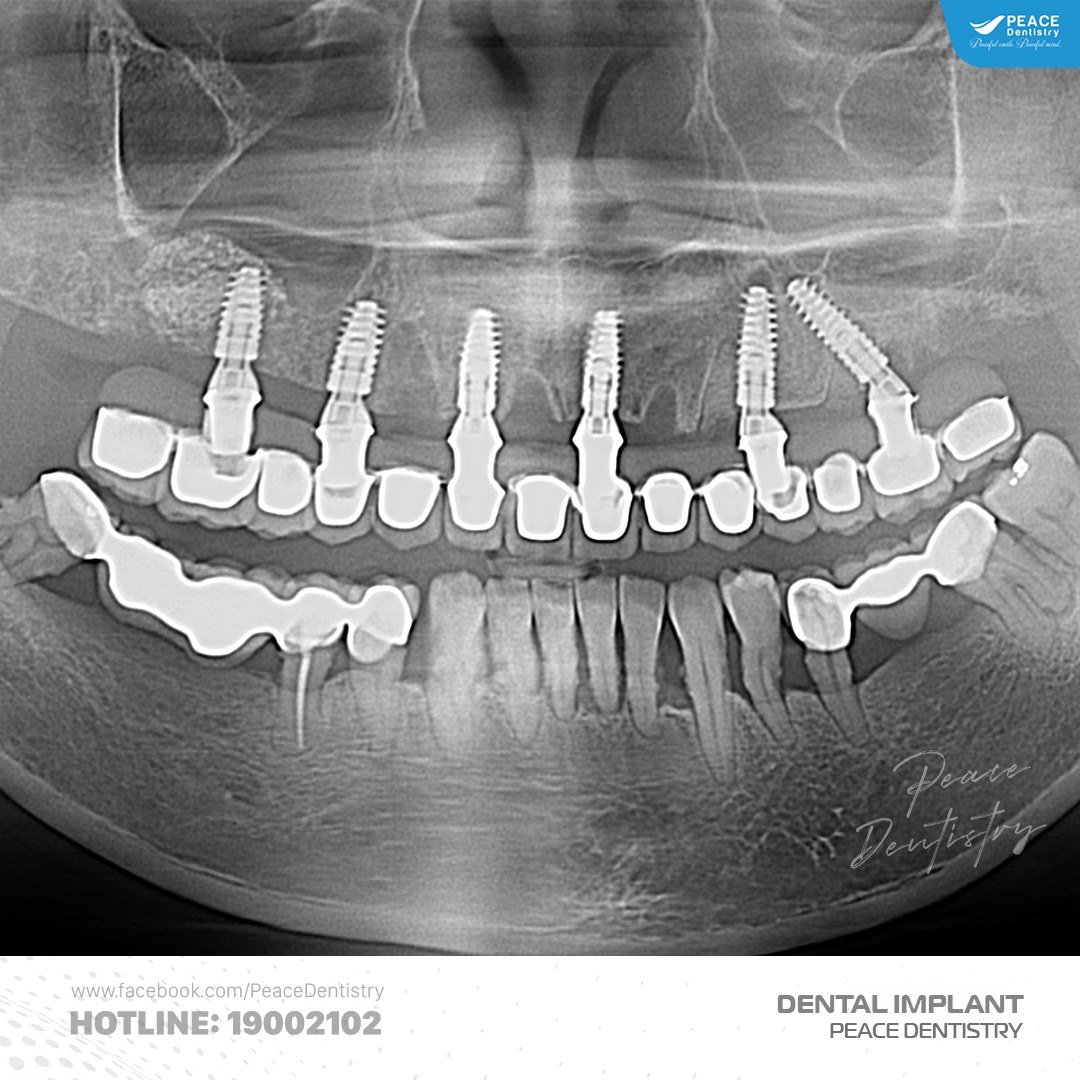

(Ca trồng răng implant có thể bị thất bại nếu không được thăm khám, kiểm tra theo đúng chỉ định của bác sĩ)(**)

Bác sĩ sẽ chỉ định chụp phim X-quang hoặc kiểm tra trực tiếp để xem quá trình tích hợp giữa trụ titanium với xương hàm